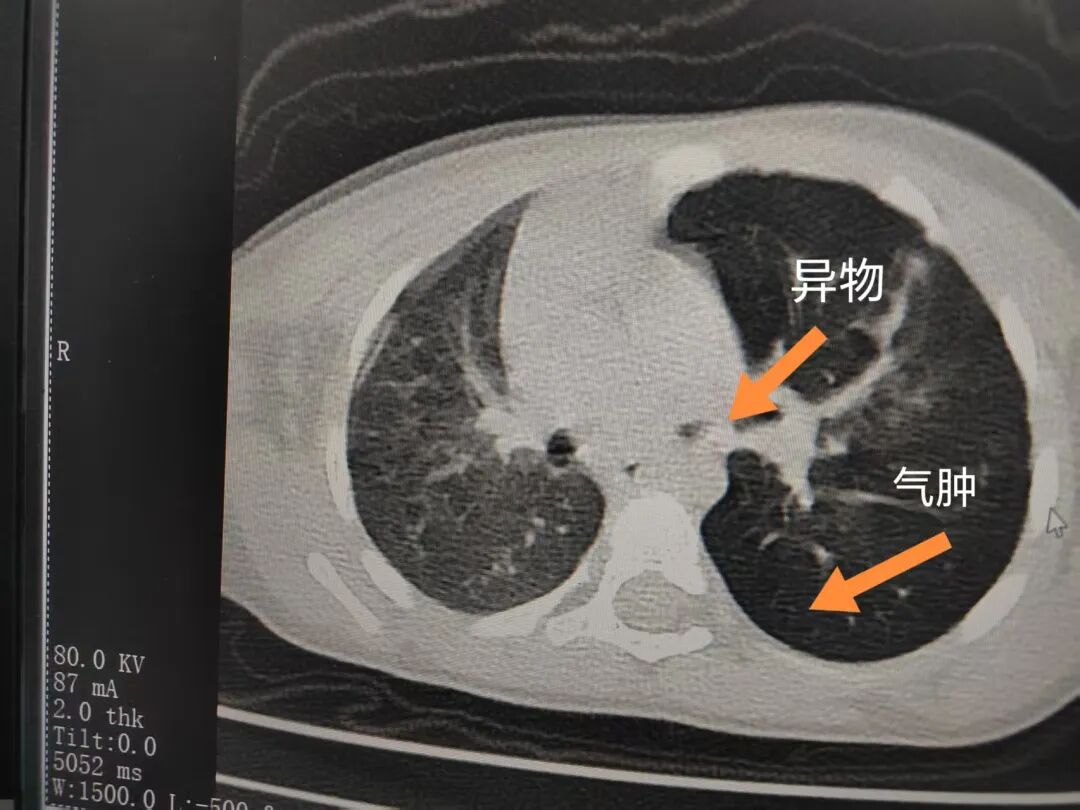

三天后(11月13日),趙寶出現(xiàn)高熱、咳喘加重,家長著急了,再次帶他來到醫(yī)院。CT檢查顯示左肺過度充氣,左肺上下葉支氣管主干見不規(guī)則高密度影,左肺上葉可見大片狀密度增高影,縱隔窗實(shí)變,提示為“左側(cè)支氣管內(nèi)異物并繼發(fā)性改變,左肺上葉舌段肺膨脹不全”。

市二院小兒呼吸內(nèi)科團(tuán)隊迅速為患兒制定了周密的手術(shù)方案,并很快安排了氣管鏡探查。術(shù)中,主治醫(yī)師田慧等憑借嫻熟的氣管鏡操作技術(shù)成功將異物大塊板栗取出。由于板栗在氣管內(nèi)存留時間較長,質(zhì)地軟糯易碎,大大增加了手術(shù)難度。檢查還發(fā)現(xiàn),異物停留部位的氣管黏膜已出現(xiàn)充血紅腫、糜爛,導(dǎo)致患兒住院時間相應(yīng)延長。此次事件給趙寶的家庭帶來了不小的驚嚇與擔(dān)憂,也再次為廣大家長敲響了警鐘。

市二院小兒呼吸內(nèi)科副主任楊亞娟介紹,異物誤入氣道可能導(dǎo)致氣道阻塞,嚴(yán)重時可引發(fā)窒息,甚至危及生命。若異物進(jìn)入支氣管,造成不完全堵塞,可引起阻塞性肺氣腫;如完全堵塞支氣管,則可能導(dǎo)致肺組織萎縮,形成肺不張。此外,若異物存留時間較長,或?yàn)橹参镄援愇?,容易合并?xì)菌感染,產(chǎn)生膿性分泌物,進(jìn)而發(fā)展為肺炎。她強(qiáng)調(diào),盡早診斷并取出異物,是減少并發(fā)癥、降低病死率的關(guān)鍵。